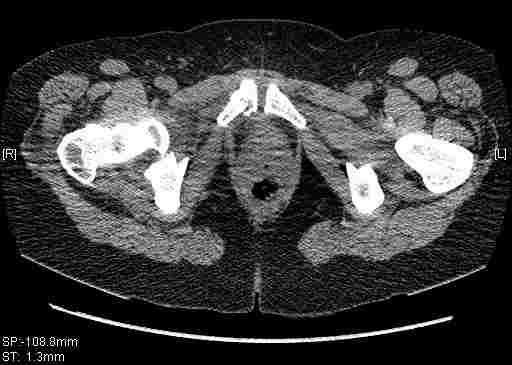

[Ortho] [1/2] Re: Т-образный перелом вертлужной впадины

Удалось сегодня вывести пациентку в соседнюю больницу, где есть кт.

Срезы сделаны  только горизонтальные.